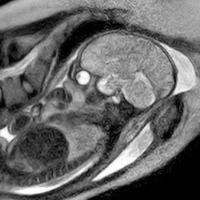

Untuk pertama kalinya di dunia, baru-baru ini seorang ibu melahirkan bayi mungil di dalam sebuah mesin MRI. Sebuah media lokal Jerman, The Local melaporkan proses kelahiran yang berlangsung lancar ini terjadi di Berlin's Charite Hospital, salah satu rumah sakit kenamaan di negara tersebut.

Namun bukan sembarang mesin MRI yang digunakan, melainkan mesin khusus yang memang didesain untuk persalinan sehingga lebih terjamin keamanannya. Selain itu ada juga tim ahli yang mendampingi, terdiri dari dokter kandungan, radiologis dan teknisi.

Selama ini, proses pergerakan bayi saat lahir masih menjadi misteri yang terus diperdebatkan. Pergerakan itu seringkali tidak lancar, sehingga bayi gagal mencapai jalan lahir dan terpaksa harus dikeluarkan melalui operasi caesar.

"Belum pernah ada penjelasan yang benar-benar memuaskan mengapa sebagian perempuan mudah saja melahirkan bayi 4,5 kg, sementara sebagian lagi kesulitan melahirkan bayi yang lebih kecil," ungkap Dr Manny Alvarez, dokter kandungan dari Hackensack University seperti dikutip dari Foxnews, Rabu (8/12/2010).

Manfaat yang diharapkan dari pengamatan tersebut antara lain untuk memahami berbagai gangguan saat melahirkan, misalnya bahu bayi yang tersangkut tulang panggul (shoulder dystocia). Menurut catatan IROC, 15 persen perempuan masa kini lebih memilih caesar untuk menghindari kemungkinan tersebut. (up/ir)